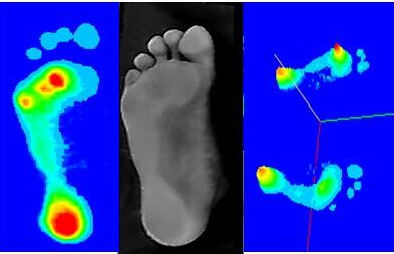

接下来,赖弘仁教授为同学们带来题为《3D扫描技术在足底矫形器中的应用》,

3D扫描,比传统方式更准确、更快速的提取足型。来自台湾的赖博士给同学们带来康复前沿的科技。

严格分析下肢力线,严格分析足底压力,结合起来判断足底情况,从而制作最有效的矫正鞋垫。透过现象看本质,找到问题的根源,才能更有效的解决问题。